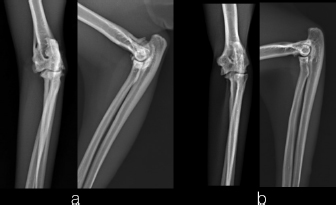

Two, spayed, Domestic Shorthaired cats with an age of 1.5 years (case 1) and 6 years (case 2) were referred to the author’s clinic for the non-weight bearing left forelimb lameness after a suspected trauma. Physical examination, of both cats, revealed moderately swollen and painful left elbow, with abnormal posture characterized by extended rotation of antebrachium and supination of the paw. Orthogonal radiographs of forelimbs demonstrated a complete caudal elbow luxation (Fig. 1). The radius and ulna were caudally and proximally displaced in relation to the humerus; furthermore, in case 1, a small avulsion bone fragment (2 mm diameter) closed to the lateral aspect of the humeral condyle was presented. No other abnormality was identified during the physical and radiographic examinations. The cats were sedated by intramuscular administration of dexmedetomidine (Dexdomitor: Pfizer Italia Srl, Rome, Italy) (10 μg/kg) and methadone (Semfortan: Dechra Veterinary Products Srl, Turin Italy) (0.4 mg/kg). General anesthesia was induced with propofol (Proposure: Merial Italia Spa, Milan, Italy) (6 mg/kg) intravenously and, after oro-tracheal intubation, maintained with isoflurane (IsoFlo: Aesica Queenborough Limited, Kent, United Kingdom) and oxygen. Modified closed reduction technique was attempted in both cases. Distal traction of antebrachium with full extension of the elbow was initially achieved followed by simultaneously applying distal pressure on the olecranon and partial elbow flexion. Following successful reduction, the collateral ligaments integrity was indirectly assessed with the Campbell’s test (1971), with normal limits value around 110° of supination and 70° of pronation recorded in both patients. The joint stability and reduction were maintained with gentle manipulation. However, instability was present at 100° of elbow extension, while major stability was obtained at 40° of flexion. For this reason, the elbow was held at 40° of flexion and a simple transarticular external skeletal fixator type IIa was applied to maintain the stability of the joint. Due to the forced flexion position, which limited the biomechanics movement, the cats were not able to weight bearing in the postoperative period. Two full pins, smooth Kirschner wires 2.0 mm of diameterf were inserted in the proximal third of the diaphysis of the humerus and in the distal third of the radial diaphysis. Stainless steel connecting bars (Gènia. St. Hilaire de Chaléons, France) (3.0 mm) were positioned medially and laterally connecting with Maynard clamps (Gènia. St. Hilaire de Chaléons, France) to the full pins (Fig. 2). The avulsion bone fragment was not treated in case 1. The patients were discharged from the clinic 24 hours after surgery. Cage rest without any exercise was recommended for 2 weeks and meloxicam (Meloxoral: Fatro S.p.A., Ozzano Emilia, Italy) (0.05 mg/kg) was administrated for 7 days.

Fig. 2. Transarticular external skeletal fixator type IIa applied to maintain the stability of the joint (case 1).